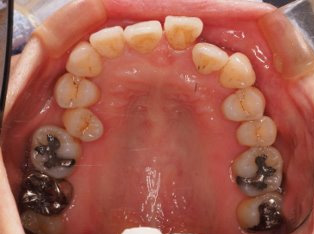

でこぼこがある状態になります。乱ぐい歯とも言われます。見た目がよくない審美障害が主な問題点ですが、その他にもでこぼこが多いことで、歯ブラシによる清掃性が悪くなり、結果、虫歯や歯周病のリスクも上がってしまいます。治療期間が短く済むことも多い為、気になった段階で早期に相談された方が良いと思います。

治療前

治療終了前